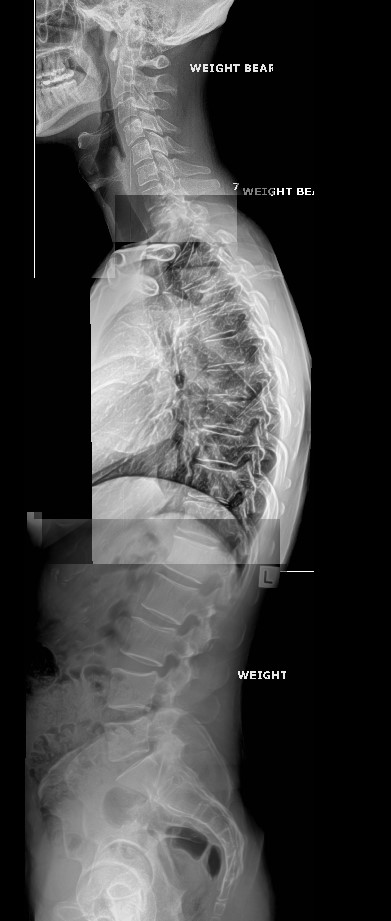

Full spine Chiropractic x-rays